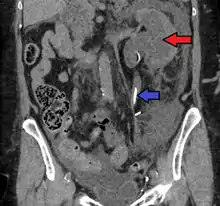

Left sided hydronephrosis in a person with an atrophic right kidney. Stent is also present (image below).

Left sided hydronephrosis, coronal view. Stent is also present.

Treatment of hydronephrosis focuses upon the removal of the obstruction and drainage of the urine that has accumulated behind the obstruction. Therefore, the specific treatment depends upon where the obstruction lies.

Acute obstruction of the upper urinary tract is usually treated by the insertion of a nephrostomy tube. Chronic upper urinary tract obstruction is treated by the insertion of a ureteric stent or a pyeloplasty.

Lower urinary tract obstruction (such as that caused by bladder outflow obstruction secondary to prostatic hypertrophy) is usually treated by insertion of a urinary catheter or a suprapubic catheter. Surgery is not required in all prenatally detected cases.[16]